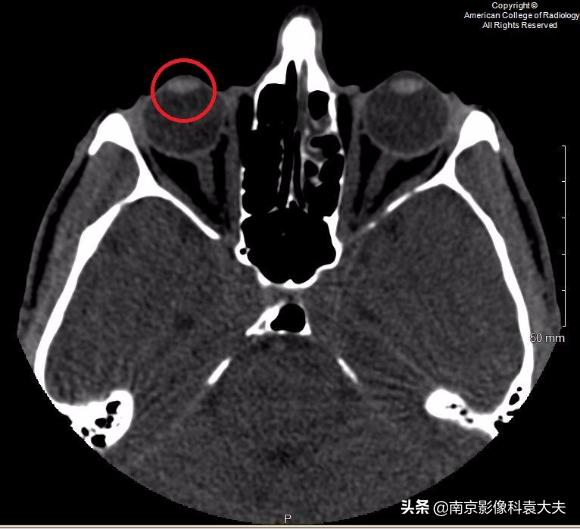

上图 在晶状体水平轴位非对比CT图像显示右眼前房(圆环)前后径减小,临床上可在角膜裂伤的情况下看到。

穿透性创伤或裂伤可能损害前房,使虹膜脱出进入前房。在CT图像上,前房液体的体积减少导致前房的前后径缩小。

前部的隐形眼镜可以类似这种表现,临床上必须予以排除。对于角膜异物,应仔细检查相关的眼球穿透伤、球后血肿和面部/眶骨折。